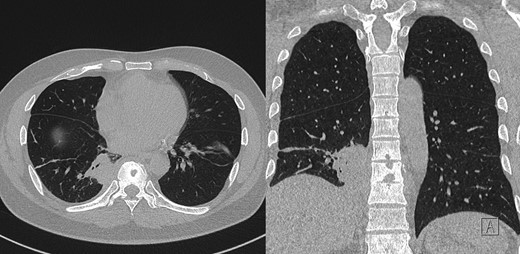

During this period he also developed osteolytic lesions of the T9/10 vertebral bodies immediately adjacent to the effusion (Fig. 1). Magnetic resonance imaging (MRI) was arranged showing T8–T10 spondylodiscitis, prevertebral and epidural phelgmons (Fig. 2), without radiological evidence of spinal cord compression. Further imaging with gallium scan showed no evidence of osteomyelitis elsewhere in the body, but unexpectedly revealed area of increased vascularity in the right iliac fossa suggestive of soft tissue infection. CT abdomen confirmed the lesion to be a peri-appendicular abscess (Fig. 3).

Post-contrast CT chest, showing ostelytic lesion of T9 vertebral body developed since original presentation and imaging. Adjacent to T9 vertebral body is area of persistent parapneumonic effusion.